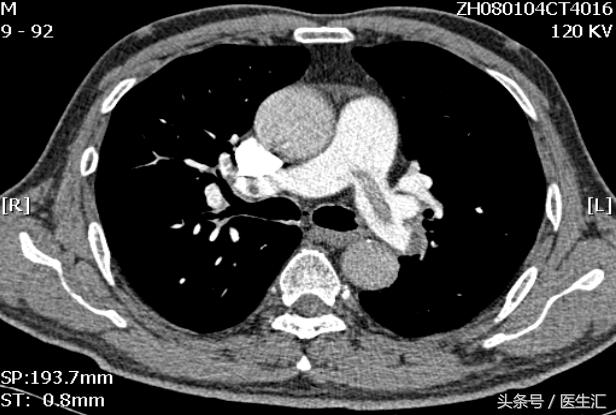

1日后肺血管急诊CT

床旁超声心动示:右肺动脉近段内探及大小约5.0×1.3cm大小的回声团块,随血流飘动;肺动脉增宽,右房和右室扩大;估测肺动脉收缩压70mmHg 。